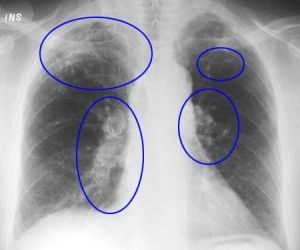

«La Fibrosis Pulmonar Idiopática provoca la muerte más precozmente que muchos tipos de cáncer, entre ellos el de mama, de ovario y colorrectal»